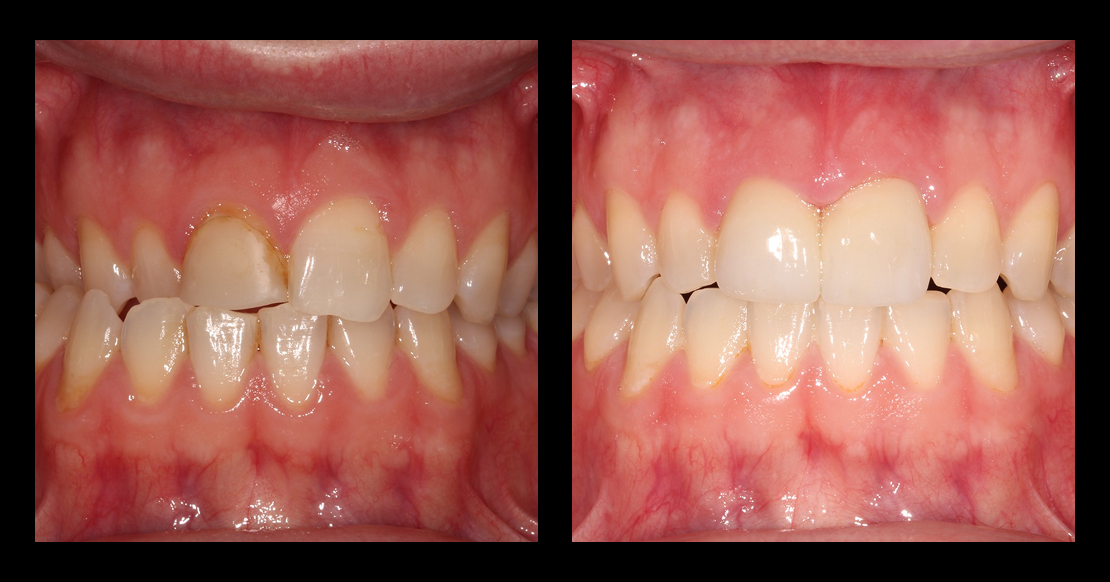

Zach, a patient in his mid-20s, came to our office seeking options for improving his upper front teeth, specifically the noticeable differences in size, shape, and shade between teeth #8 and #9. A childhood bicycle accident had left #8 chipped, and multiple composite restorations over the years hadn’t given him the esthetics he hoped for.

Taking an FGTP approach quickly revealed why restoring #8 had been so challenging. A crossbite was limiting available restorative space, and the gingival position of #8 was more coronal than #9, suggesting supereruption after the original trauma.

The more conservative and airway-conscious option was an orthodontic–restorative approach. Orthodontics could correct the crossbite, level the gingival margins, and restore harmony to the occlusal relationship.

Once the teeth were in their proper positions, we could address #8 and #9 with a single crown and veneer.

Clear aligners with attachments and elastics were used to correct the crossbite and improve tooth position. After 18 months, Zach’s teeth were in an ideal position for restorative care.

With the attachments removed, we prepared #8 and #9 and placed a diagnostic provisional to test esthetics and function. After one month with no occlusal adjustments needed, we moved forward with the definitive porcelain restorations.